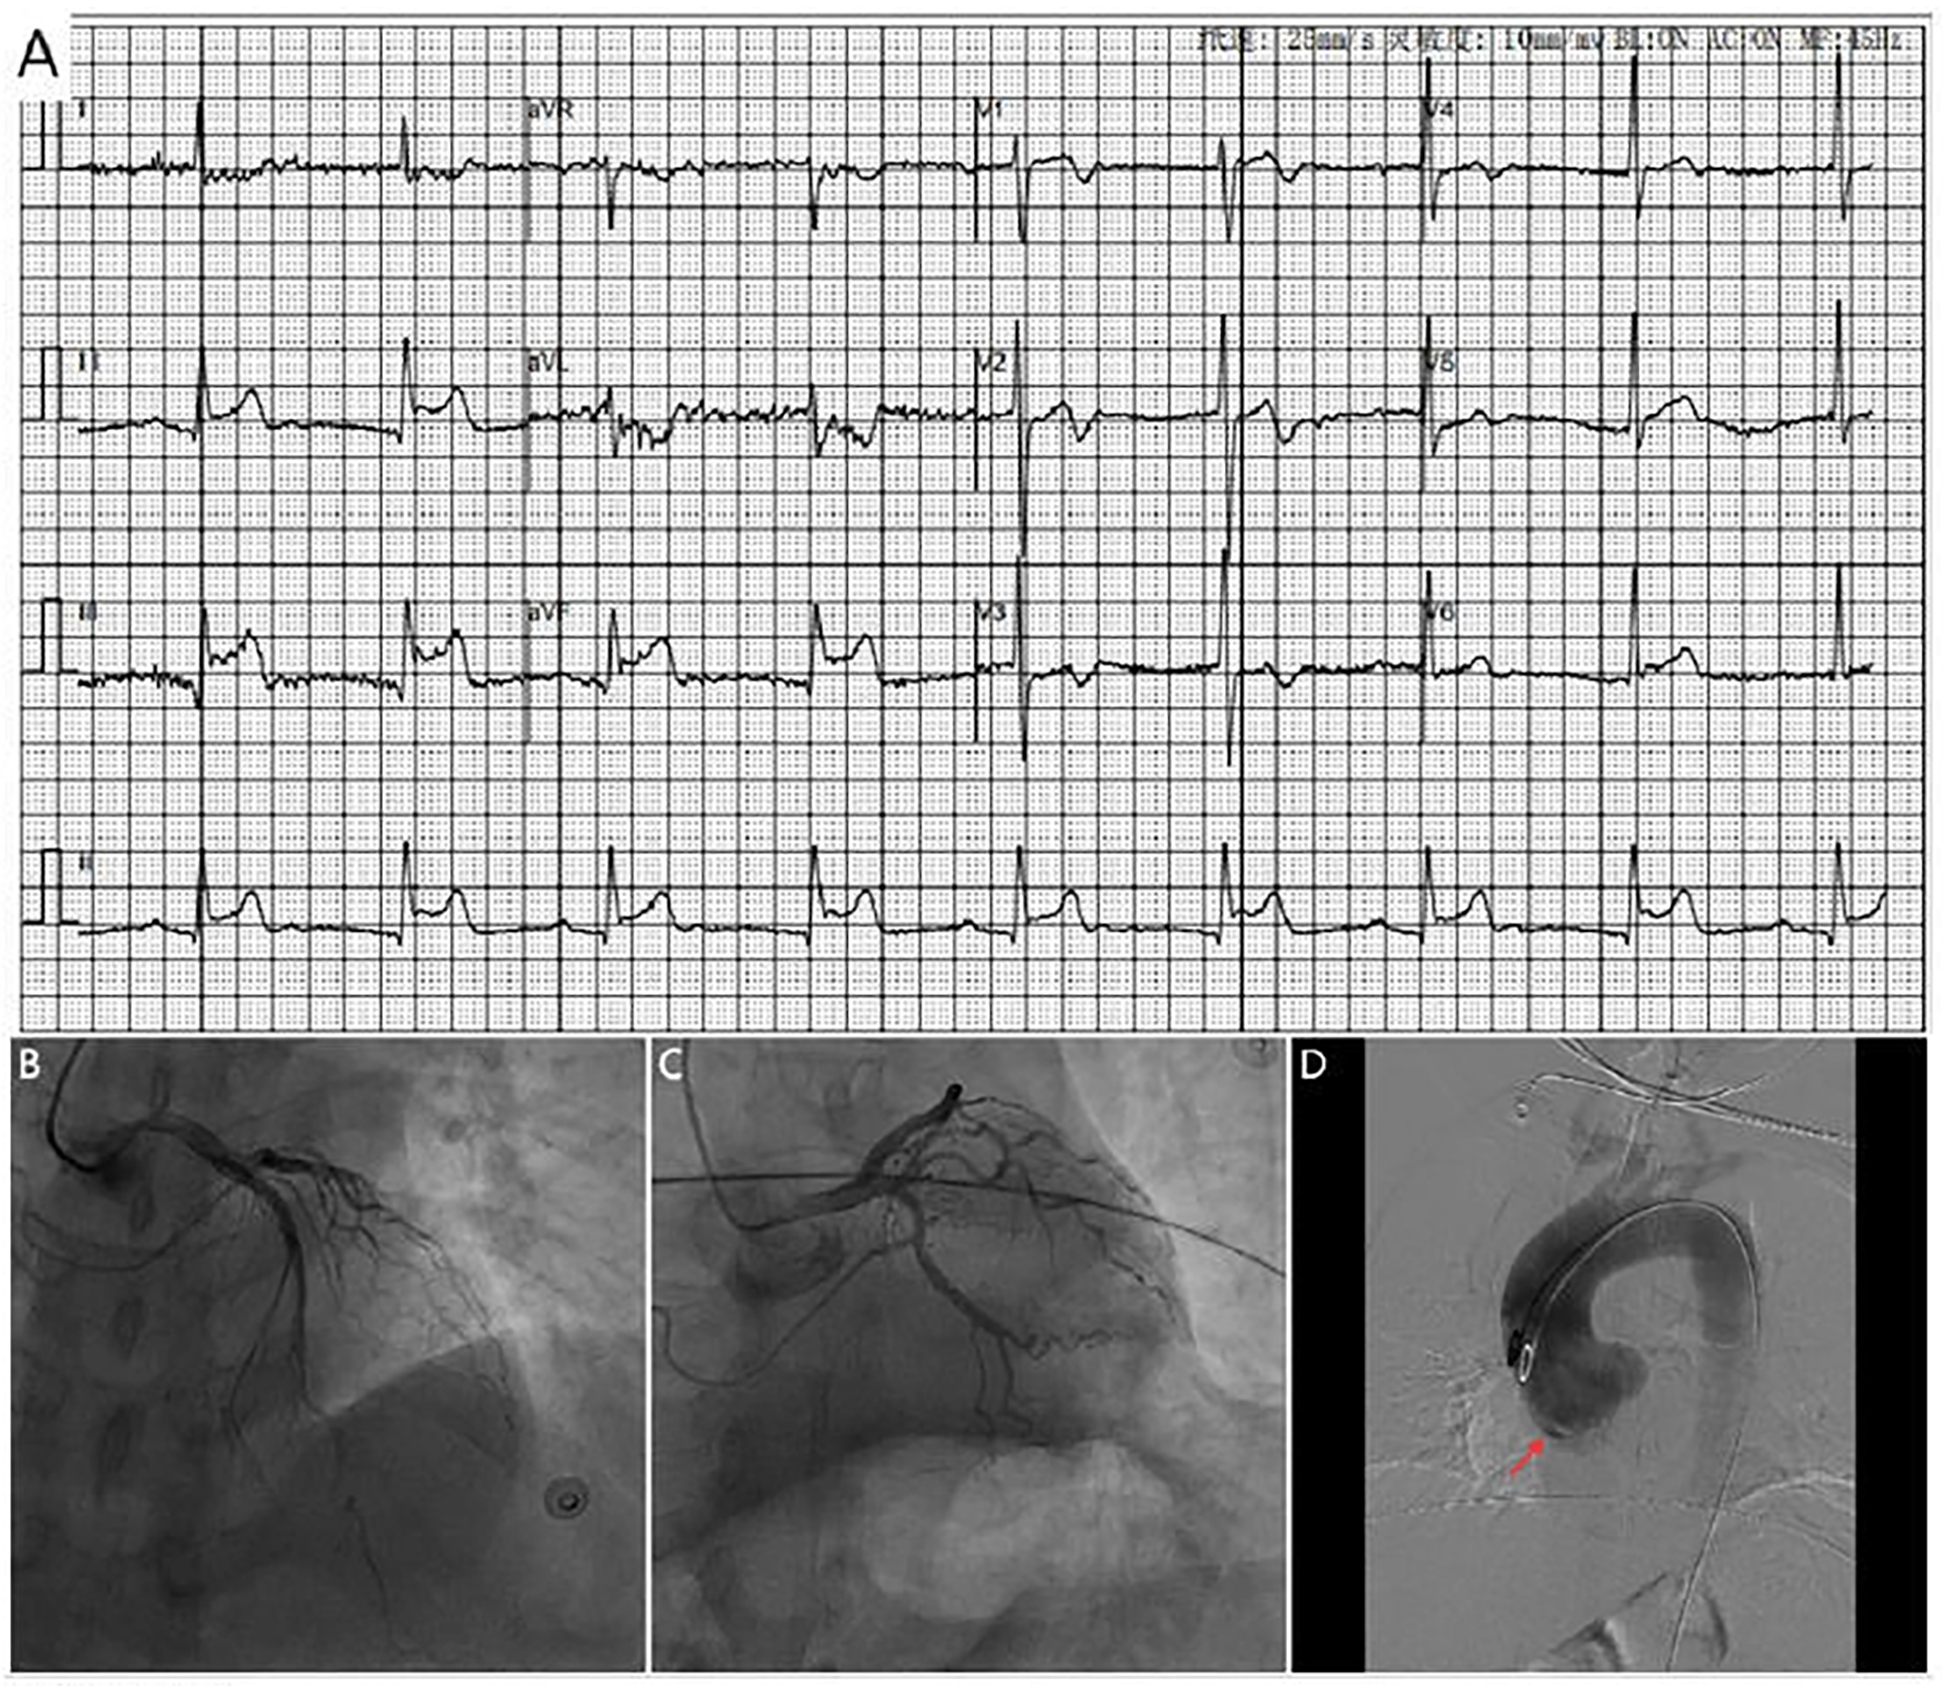

A 42-year-old man with no known comorbidities and a family history of AD presented with sudden-onset chest pain during esports gameplay. ECG showed inferior STEMI with complete heart block (Figure 1A). CAG revealed a normal left coronary system, but the RCA could not be engaged. Aortic root angiography showed no anomalous origin of the RCA; however, it suggested a possible dissection of the right SOV (Figures 1B–D; Supplementary Video 1). CTA revealed ascending aortic dilation and a localized dissection of the right SOV (Figures 2A–C; Supplementary Video 2). The emergency transthoracic echocardiography (TTE) revealed dilation of the ascending aorta, measuring 43 mm in diameter. Despite the recommendation for immediate surgery, family hesitation delayed intervention. The operative findings showed that a dissection of SOV extending into the RCA ostium. Coronary artery bypass grafting (CABG) and sinus reconstruction were performed, however the patient developed cardiogenic shock and refractory ventricular arrhythmias. The family declined mechanical circulatory support (MCS), and the patient subsequently died.

Figure 1

(A) ECG shows marked ST-segment elevation in leads II, III and avF, along with complete heart block (B,C). Coronary angiography shows no significant stenosis in the left coronary artery. (D) Aortic angiography reveals possible dissection of the right coronary sinus of valsava (red arrow).